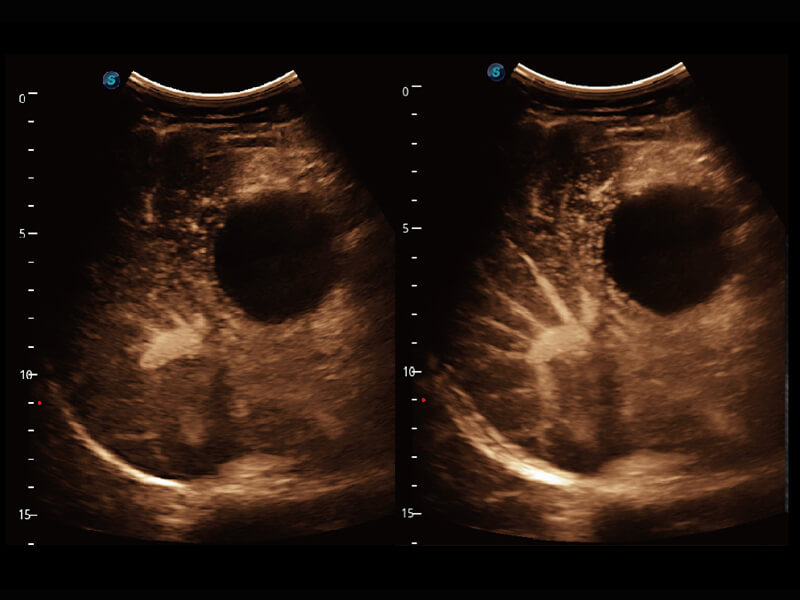

成像功能

性能优异的硬件架构,极大提升超声系统的运行效率和数据处理能力。相比以往超声成像系统,Wis+平台为您带来极快的响应速度和成像帧频,提升检查流畅度。

S60探头工艺,从前端信号处理每一个环节采集无损声学数据,真实还原组织原貌,再现解剖细节。